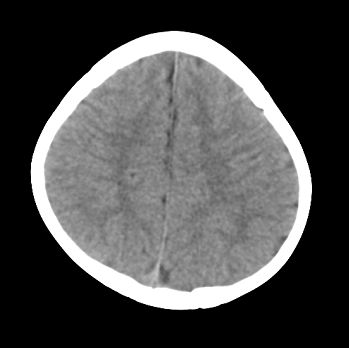

以下是引用jiangjing在2008-6-9 8:33:00的发言:[br]病灶周围见脑组织包绕,上部可见等或稍高密度壁环绕,壁且见小点钙化-----考虑皮样囊肿或表皮样囊肿可能